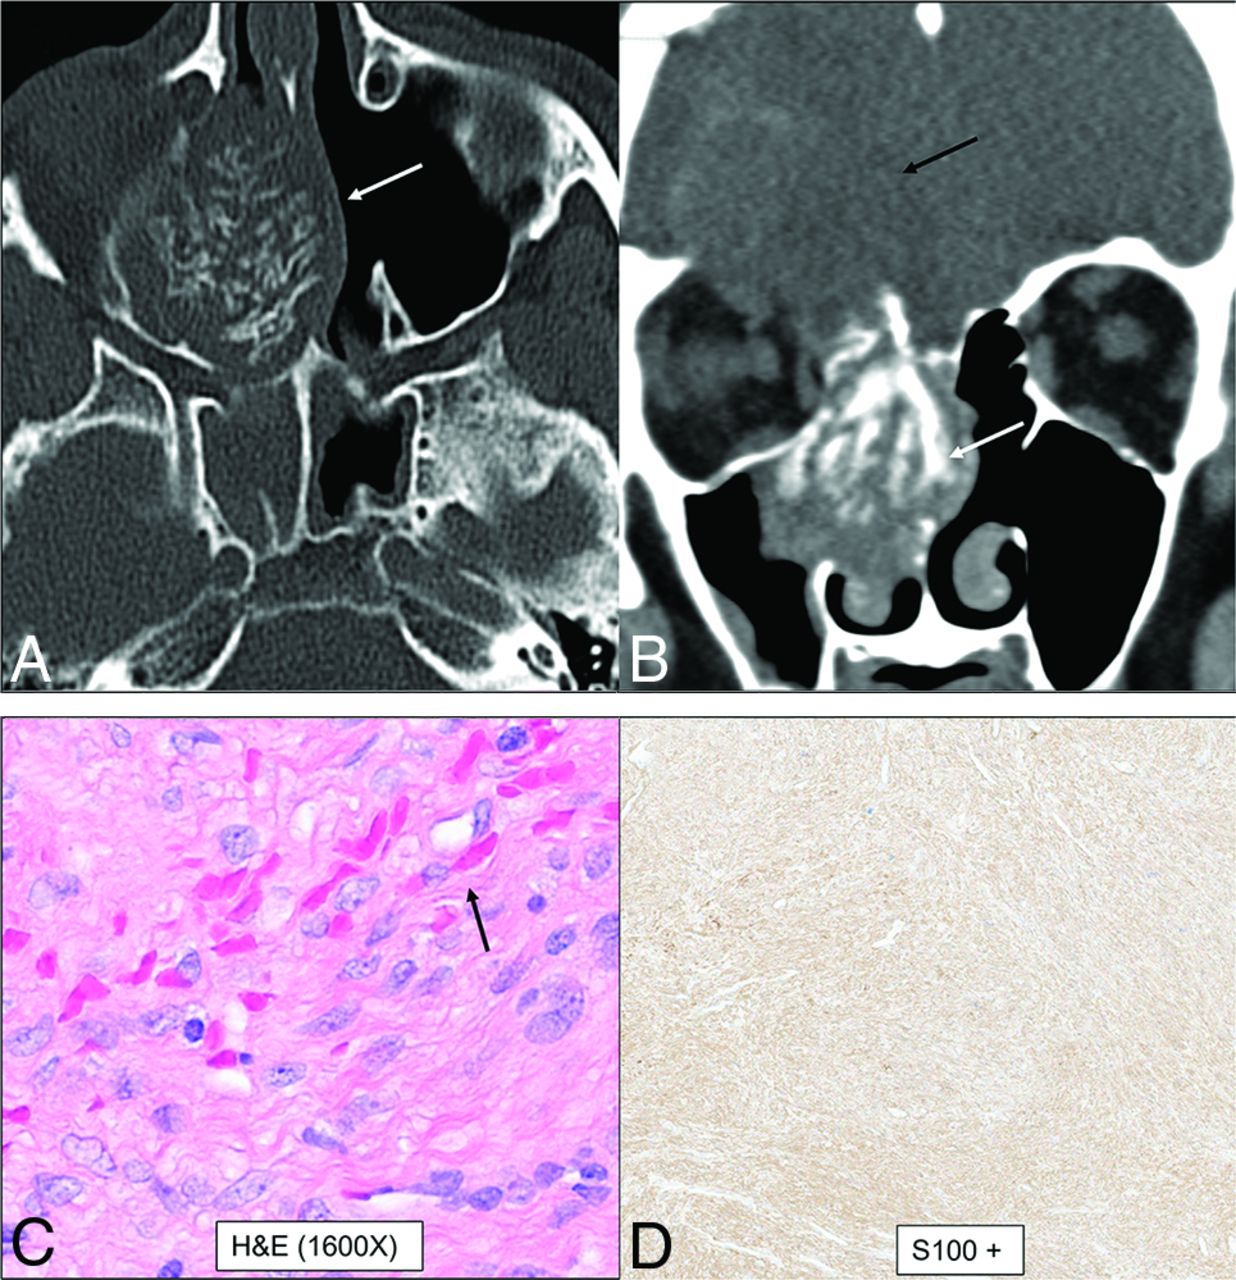

Multiple categories of tumor have been separately described in the new edition, including benign soft-tissue tumors and borderline, low-grade malignant soft-tissue tumors. However, some soft-tissue tumors that occur exclusively or predominantly in the sinonasal region were retained in the newly created category of mesenchymal tumors. These include angiofibroma, glomangiopericytoma, biphenotypic sinonasal sarcoma, and chordoma. Among these, biphenotypic sinonasal sarcoma is the relatively recent entity, introduced only in the 4th edition (2017).1,2 These tumors have neural and myogenic features and are histologically similar to cellular schwannomas or malignant peripheral nerve sheath tumors. Rearrangement of the PAX3 gene is required for the diagnosis of these tumors. They are characteristically seen in middle-aged women, arising from the nasal cavity or ethmoid sinus. Imaging reveals locally aggressive nasoethmoid-enhancing masses that can erode through the orbits and skull base with frequent hyperostotic bony changes (Fig 8).

Biphenotypic sinonasal sarcoma (low-grade sinonasal sarcoma with neural and myogenic features) in a 68-year-old woman. Marked intralesional hyperostotic changes are noted within the nasal component of the tumor (A and B, white arrows). The tumor is well-marginated but locally aggressive with intracranial extension (B, black arrows). H&E stain (C) shows the tumor growing as fascicles of uniform spindle cells with minimal mitotic activity or atypia and overt rhabdomyoblastic differentiation in the form of strap cells (C, arrow). Diffusely positive staining of S-100 (nerve sheath tumor marker) seen as diffuse brown staining (D). Fluorescence in site hybridization testing was positive for PAX3 gene rearrangement, supporting the above diagnosis.